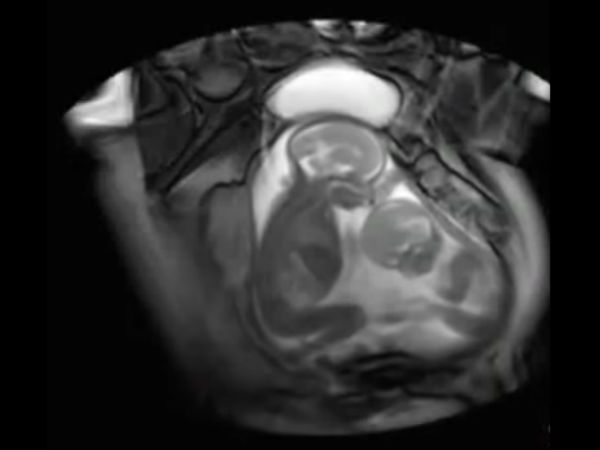

ഇരട്ടക്കുട്ടികള് വയറ്റിനകത്ത് തന്നെ അടിപിടി

ഇരട്ടക്കുട്ടികള് ഗര്ഭപാത്രത്തിനകത്ത് വെച്ച് അടിയും ചവിട്ടും എന്നു വേണ്ട എല്ലാ കലാപരിപാടികളും ഉണ്ട്

വളരെ അപൂര്വ്വമായി മാത്രമേ ഇത്തരം കാഴ്ചകള് ക്യാമറയ്ക്കുള്ളില് പതിയാറുള്ളൂ എന്നാണ് ഡോക്ടര്മാര് പറയുന്നത്. ലണ്ടനില് നടന്ന ഒരു പഠനത്തിനിടെയാണ് ഇടി കൂടുന്ന ഇരട്ടക്കുട്ടികളെ കണ്ടെത്തിയത്.

എം ആര് ഐ സ്കാന്

സിനി എം ആര് ഐ സ്കാന് എന്ന നൂതന വിദ്യയുടെ സഹായത്തോടു കൂടിയാണ് ഇത്തരമൊരു രംഗം ചിത്രീകരിയ്ക്കപ്പെട്ടത്. ട്വിന് ടു ട്വിന് ട്രാന്സ്ഫ്യൂഷന് സിന്ഡ്രോം എന്ന അവസ്ഥയാണ് ഇത്.

പരസ്പരം അടി

രണ്ട് പേരും കൂടി പ്ലാസന്റ ഷെയര് ചെയ്യുമ്പോള് അസാധാരണമായ രക്തകോശങ്ങള് ഉണ്ടാവുന്നു. ഇത് കുട്ടികളില് ഒരാള്ക്ക് പോഷകങ്ങള് കുറവ് കിട്ടാന് കാരണമാകുന്നു.

എന്തിന് വേണ്ടിയാണ് ഇത്തരത്തില് അടി കൂടുന്നതെന്നതാണ് അറിയാത്തത്. ഇനി കിടക്കാന് സ്ഥലമില്ലാത്തത് കൊണ്ടാവുമോ? എന്നാല് അടി കിട്ടുന്ന ആള് അതൊന്നും തിരിച്ച് കൊടുക്കാതെ എല്ലാം കൊള്ളുകയാണ്. എപ്പോഴെങ്കിലും തിരിച്ച് കൊടുക്കാമെന്ന പ്രതീക്ഷയായിരിക്കും.